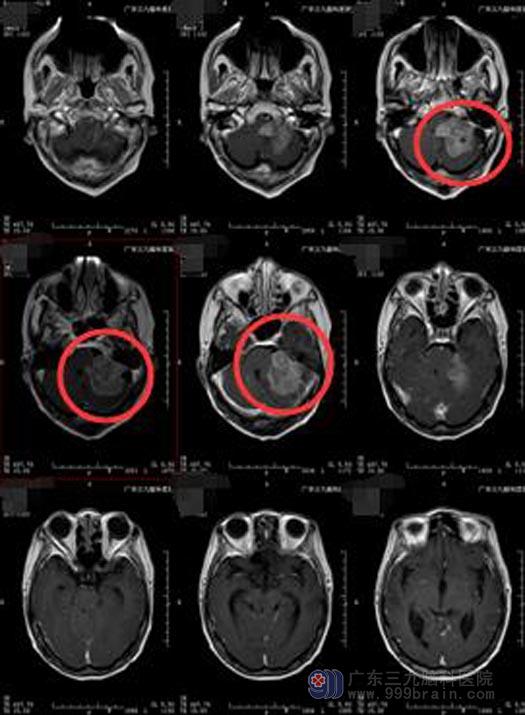

肖爷爷两年前头痛头晕,当地医院检查结果是“左侧桥小脑角区占位病变,考虑脑膜瘤”。家里人考虑到肖爷爷已是80出头的老人,有过脑梗病史,一直伴有痛风、高血压等疾病,担心老人承受不了手术风险,所以就一直拖着。

完善各项术前准备后,鲁明副院长主刀,在全麻下行左侧桥小脑角占位切除术,术中见肿瘤与周围关系密切,前下方受压三叉神经及滑车神经,肿瘤脑干面粘连紧密,利用钨针、超声吸引器、电生理监测等技术将肿瘤分块切除,手术过程顺利。

术后肖爷爷神志清醒,无面瘫、口角歪斜、吞咽困难等后组颅神经损害症状,已康复出院。术后病理回报:过渡型脑膜瘤,WHO I级。

手术前

手术后